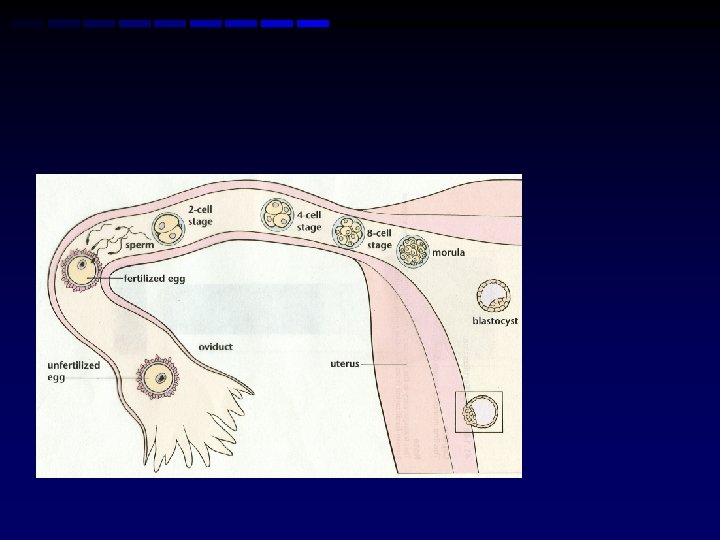

1 Day Post-Ovulation • Sperm fertilizes egg • Creation of ZYGOTE

1. 5 – 3 Days Post-Ovulation Development Picture • Cleavage of zygote-picture • First cell divisions repeat approximately every 20 hours • When cell division creates about 16 cells, the mass is called a MORULA • Morula leaves oviduct to uterus 3 -4 days after fertilization

Day 4 (Week 1) Development Picture • Early Blastocyst phase • In uterus, cell division continues • Cells move to outer areas leaving open cavity inside—this is called the BLASTOCYST (Blastula)

Day 5 -6 (Week 1) Development Picture • Implantation Begins • Considered pregnant • Progesterone produced to maintain thickness of uterine lining